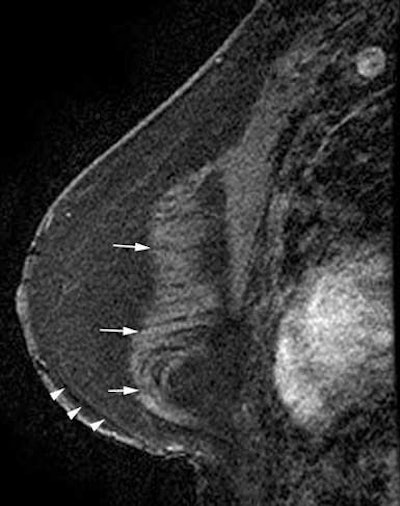

Reconstruction with latissimus dorsi myocutaneous flap: Latissimus dorsi muscle, fat and skin are rotated to reconstruct the breast. Top: Sagittal fat-saturated T1-weighted image shows latissimus dorsi muscle flipped anteriorly for reconstruction (white arrows) and the denuded dermal layer is seen parallel to the chest wall (white arrow heads). Bottom: Axial fat-saturated T1-weighted subtraction image with postcontrast gadolinium injection, the flap consisting of the latissimus dorsi muscle and its overlying skin and fat flipped and tunneled from the back to the neobreast (white arrow), giving a tailed appearance to the muscle in the lateral breast. This can be used as a differentiator on imaging from transverse rectus abdominis myocutaneous (TRAM) flap reconstruction. All images courtesy of Dr. Vandana Dialani.